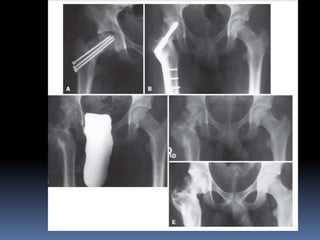

 RADIOLOGICAL APPEARANCES-

 Plain x-rays are taken in AP & lateral view (frog leg)

 PRESLIP STAGE:

 Minimal slip – absence of normal shoulder on upper aspect of neck & head-

trethowan sign ;line drawn along superior surface of neck will pass above

head.

 Head is sickle shaped.

 Epiphyseal plate widened with streaks of sclerosis.

 Lat view – slightest backward displacement

 EARLY STAGE:

 Head of femur rotated - displaced downwards & laterally.

 Lower margin of head projecting as beak like process below the lower

margin of neck.

 Upper margin of head thinned out.

 Femur neck – upper border is lengthened & convex upward , lower border

is concave & shortened.

 ADVANCED STAGE:

 Head is atrophic , grossly rotated & displaced.

 Projecting lower edge of head is curved laterally & upwards – is in contact

with lower border of neck.

 Neck is thick & short , sharply bowed upwards.

 Neck-shaft angle appears decreased to about 90 deg.

 Severe displacement – head is completely separated from neck & lies loose

in acetabulum.

 INTERTROCHANTERIC OSTEOTOMY:

Capital epiphysis slipped chronically & united in poor position, then

trochanteric osteotomy done to produce opposite deformity.

If physis remains open, need to be fixed with pins or screws.

To correct coxa vara with some external rotation & hyperextension ,

closing wedge trochanteric osteotomy, with base of wedge laterally is

sufficient.

To correct coxa vara, hyperextension & moderate or severe external

rotation , ball & socket osteotomy at lesser trochanter can be done.